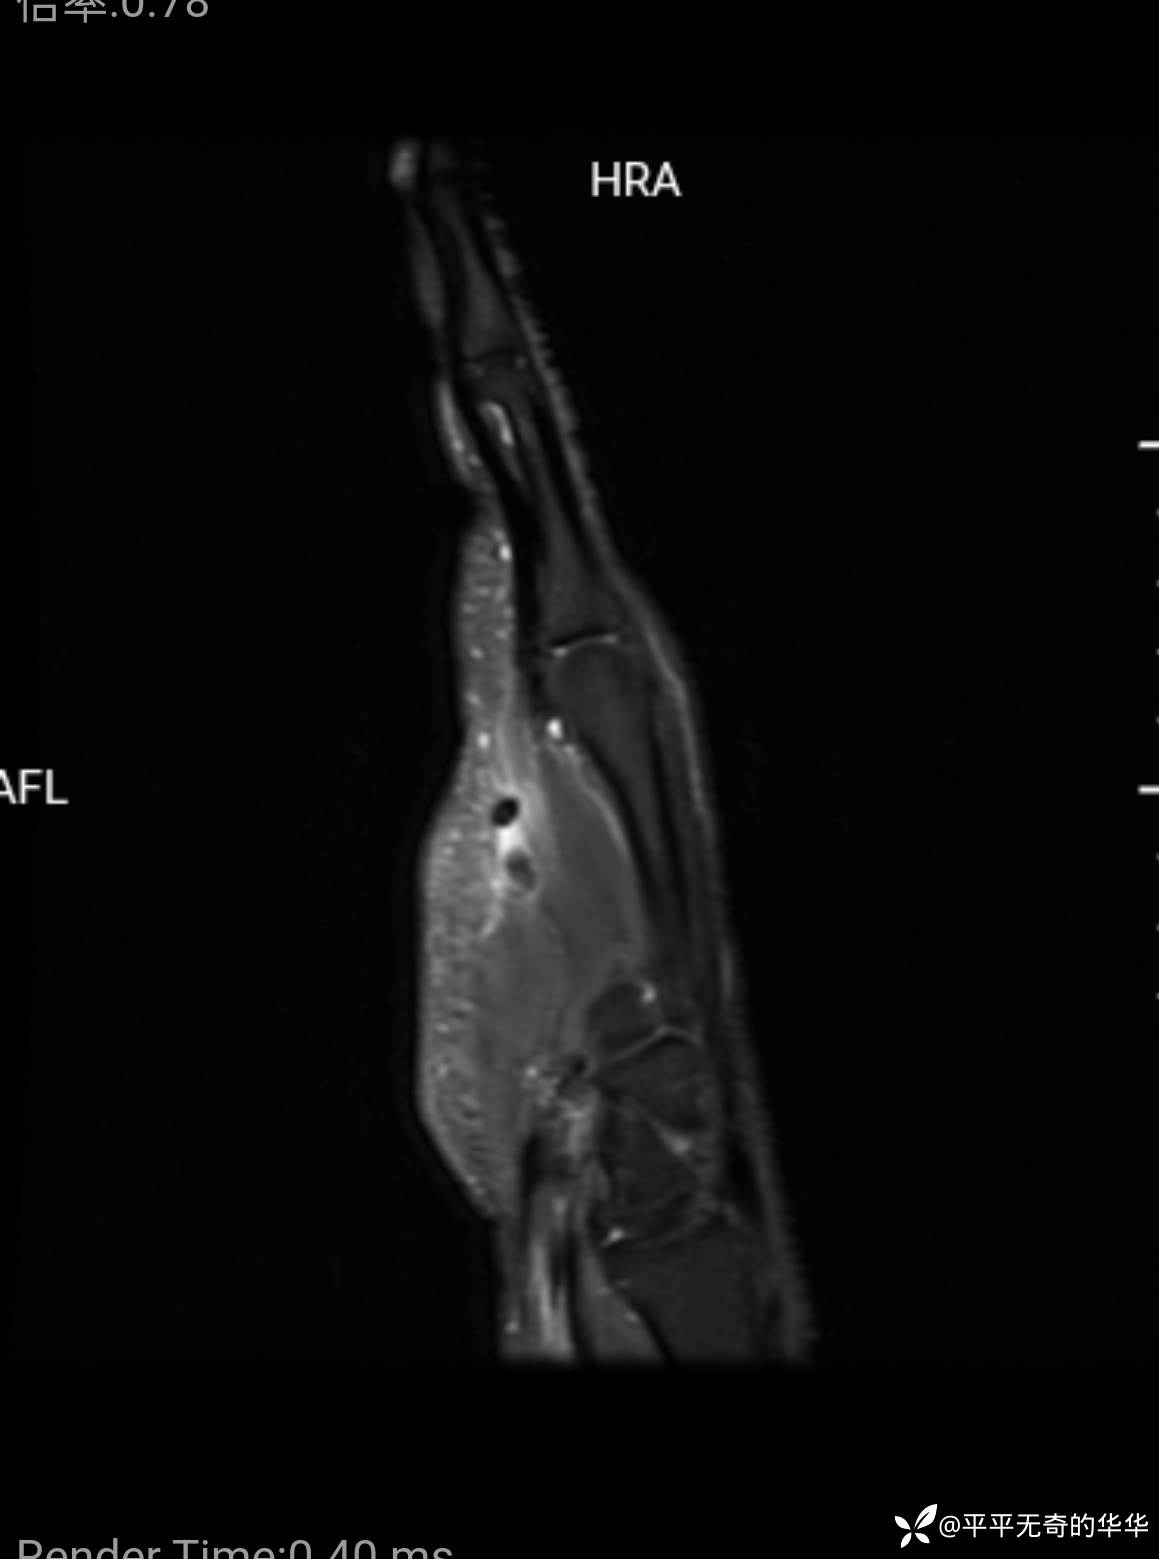

右小指屈肌腱磁共振影像,未见肌腱走行